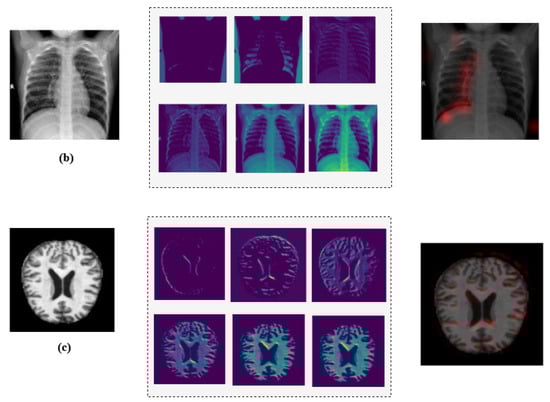

A Hybrid Convolutional Neural Network–Long Short-Term Memory (CNN–LSTM)–Attention Model Architecture for Precise Medical Image Analysis and Disease Diagnosis

Background: Deep learning (DL)-based medical image classification is becoming increasingly reliable, enabling physicians to make faster and more accurate decisions in diagnosis and treatment. A plethora of algorithms have been developed to classify and analyze various types of medical images. Among them, Convolutional Neural Networks (CNNs) have proven highly effective, particularly in medical image analysis and disease detection. Methods: To further enhance these capabilities, this research introduces MediVision, a hybrid DL-based model that integrates a vision backbone based on CNNs for feature extraction, capturing detailed patterns and structures essential for precise classification. These features are then processed through Long Short-Term Memory (LSTM), which identifies sequential dependencies to better recognize disease progression. An attention mechanism is then incorporated that selectively focuses on salient features detected by the LSTM, improving the model’s ability to highlight critical abnormalities. Additionally, MediVision utilizes a skip connection, merging attention outputs with LSTM outputs along with Grad-CAM heatmap to visualize the most important regions of the analyzed medical image and further enhance feature representation and classification accuracy. Results: Tested on ten diverse medical image datasets (including, Alzheimer’s disease, breast ultrasound, blood cell, chest X-ray, chest CT scans, diabetic retinopathy, kidney diseases, bone fracture multi-region, retinal OCT, and brain tumor), MediVision consistently achieved classification accuracies above 95%, with a peak of 98%. Conclusions: The proposed MediVision model offers a robust and effective framework for medical image classification, improving interpretability, reliability, and automated disease diagnosis. To support research reproducibility, the codes and datasets used in this study have been publicly made available through an open-access repository. Full article

Show Figures

Figure 1